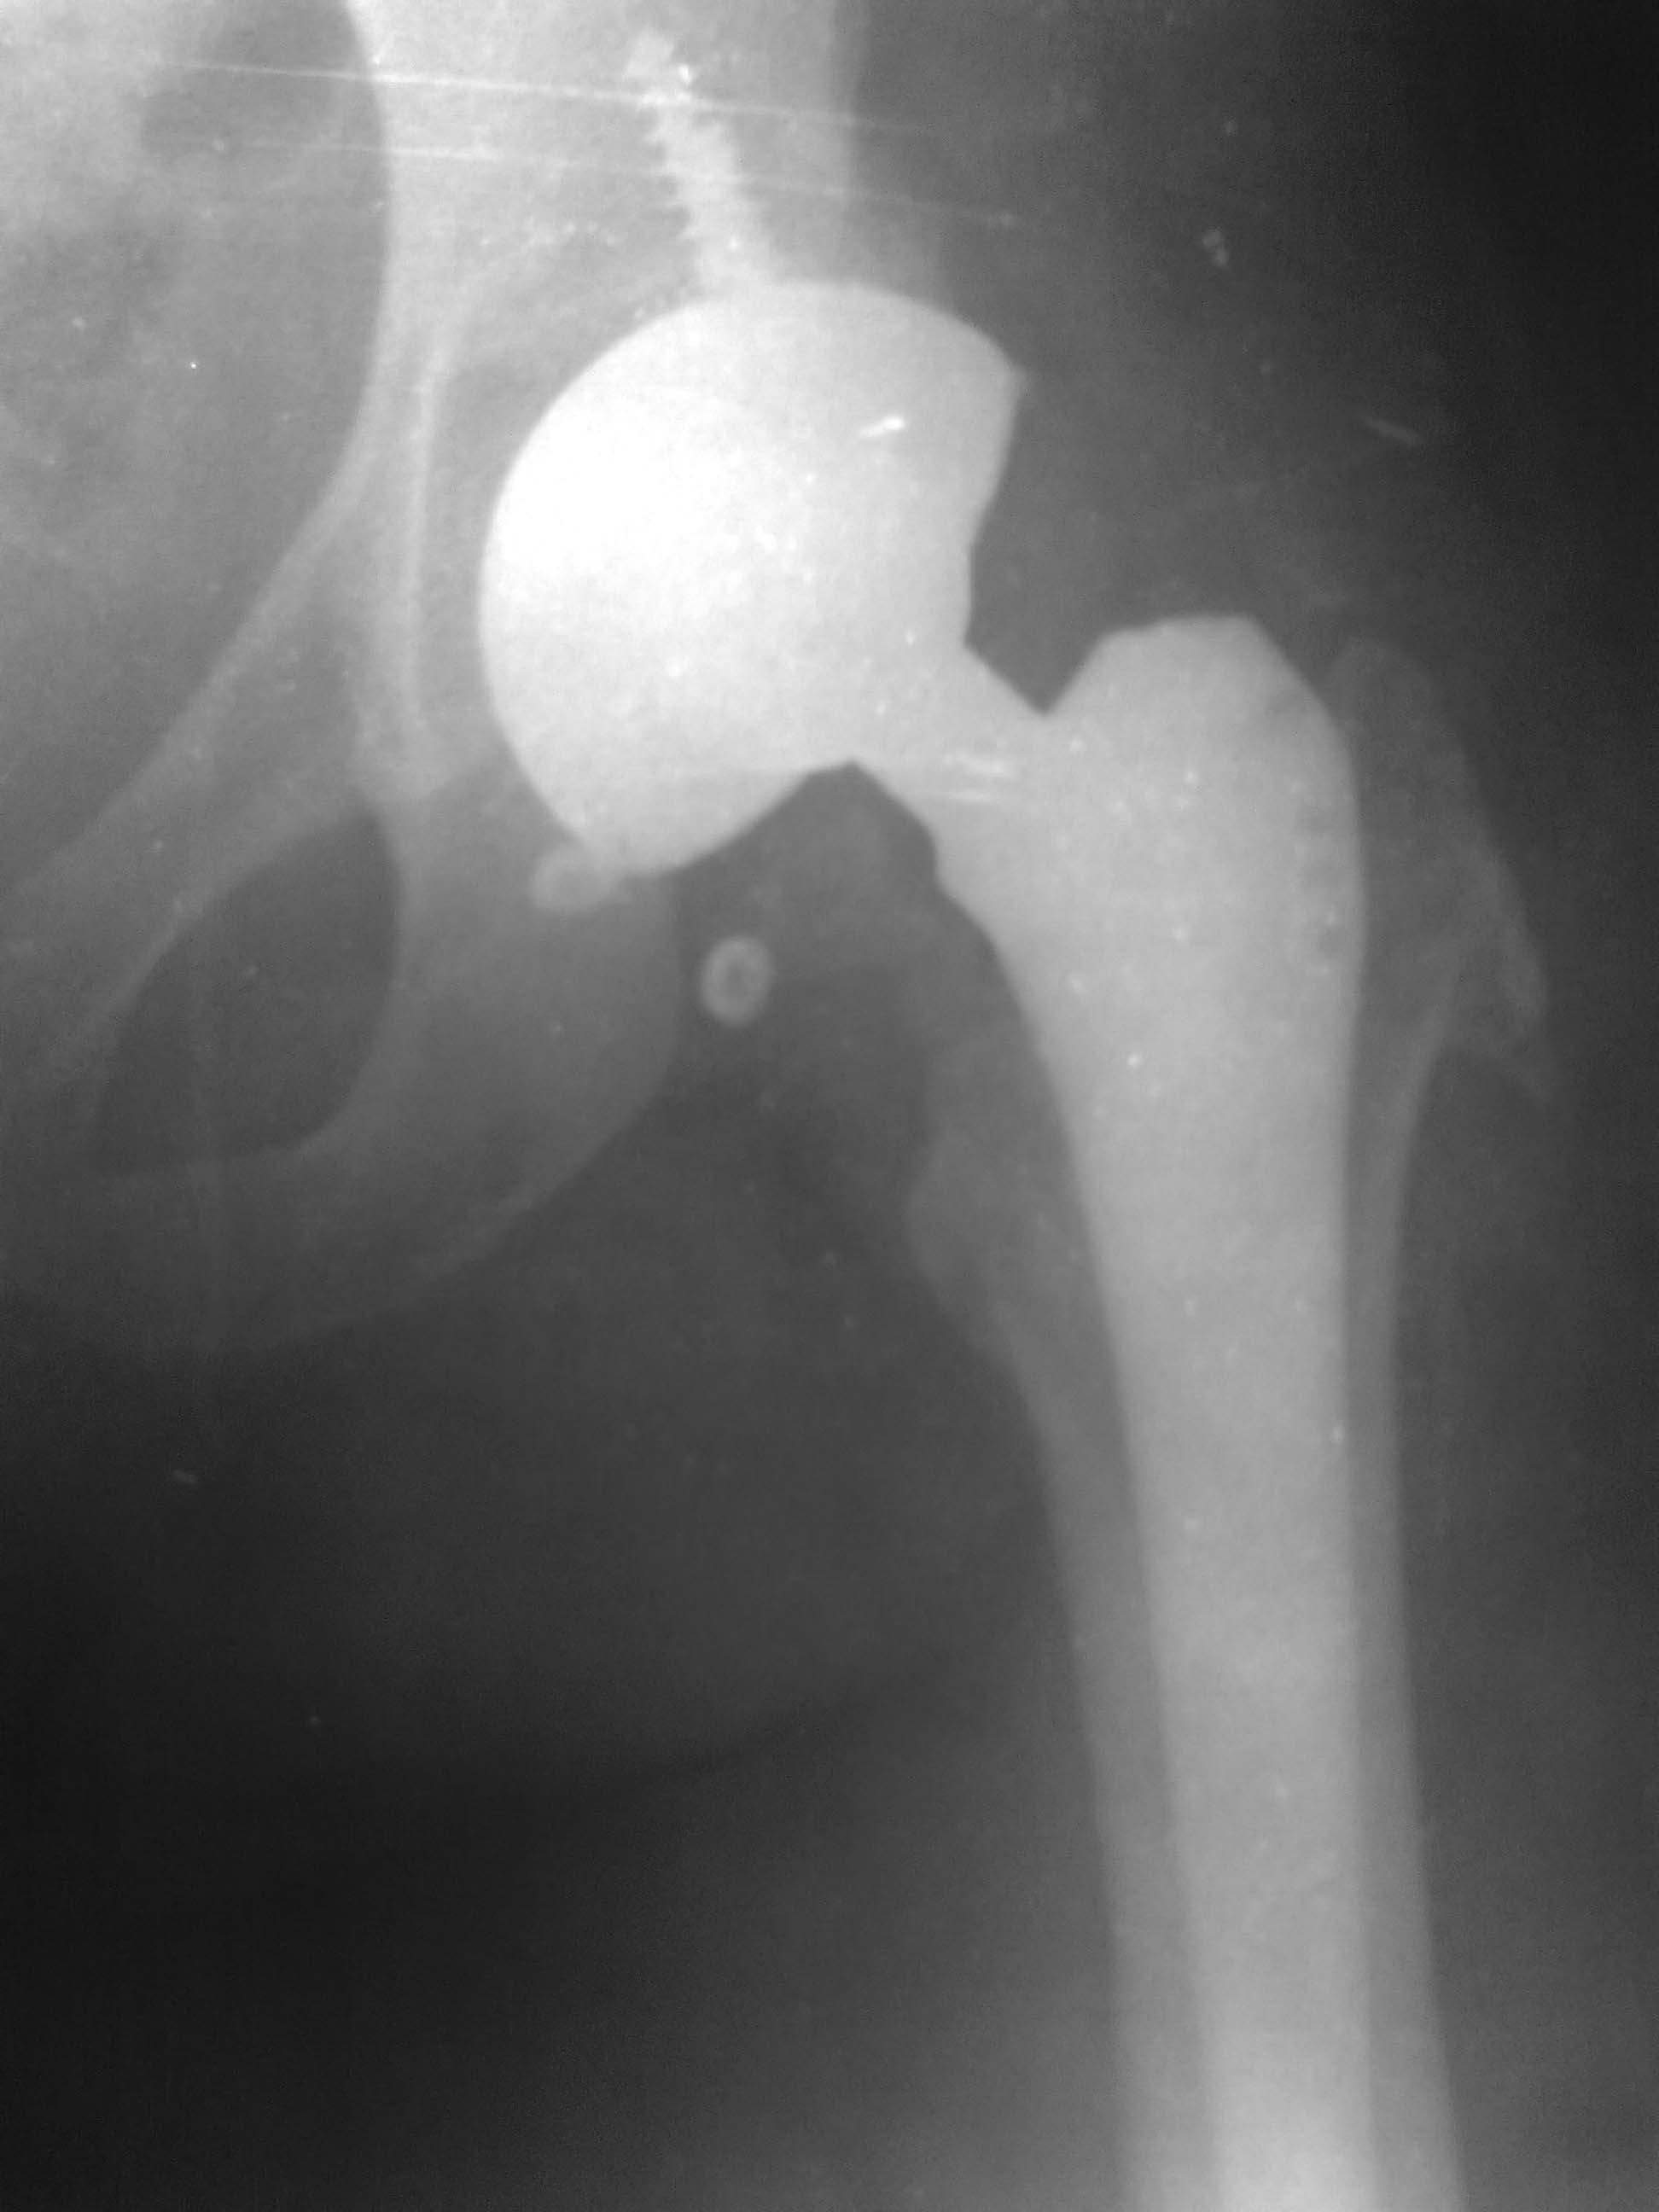

Мне кажется, что угол инклинации вертлужного компонента превышает 45 градусов,но чтобы правильно ценить этот угол, нужно выполнить обзорный снимок таза с тазобедренными суставами и потом измерить угол инклинации чашки. К тому же, чашка при установке латерализовано- мне так кажется-истинная вертлужная впадина находится чуть глубже. Конечно, медиализация чашки увеличит расстояние между бедром и центром вращения чашки (оффсет). http://bone-surgery.ru/view/oslozhneniya_posle_endoprotezirovaniya_tazobedrennogo_sustava_vyvihi_bedra/ по этой ссылке найдете статью, как раз по этой теме.

Ну вот, другое дело. Сравните снимке до и после, увидете разницу, насколько разнятся стояния чашек и по глубине и по углу инклинации.Молодцы. Я Вас Поздравляю.